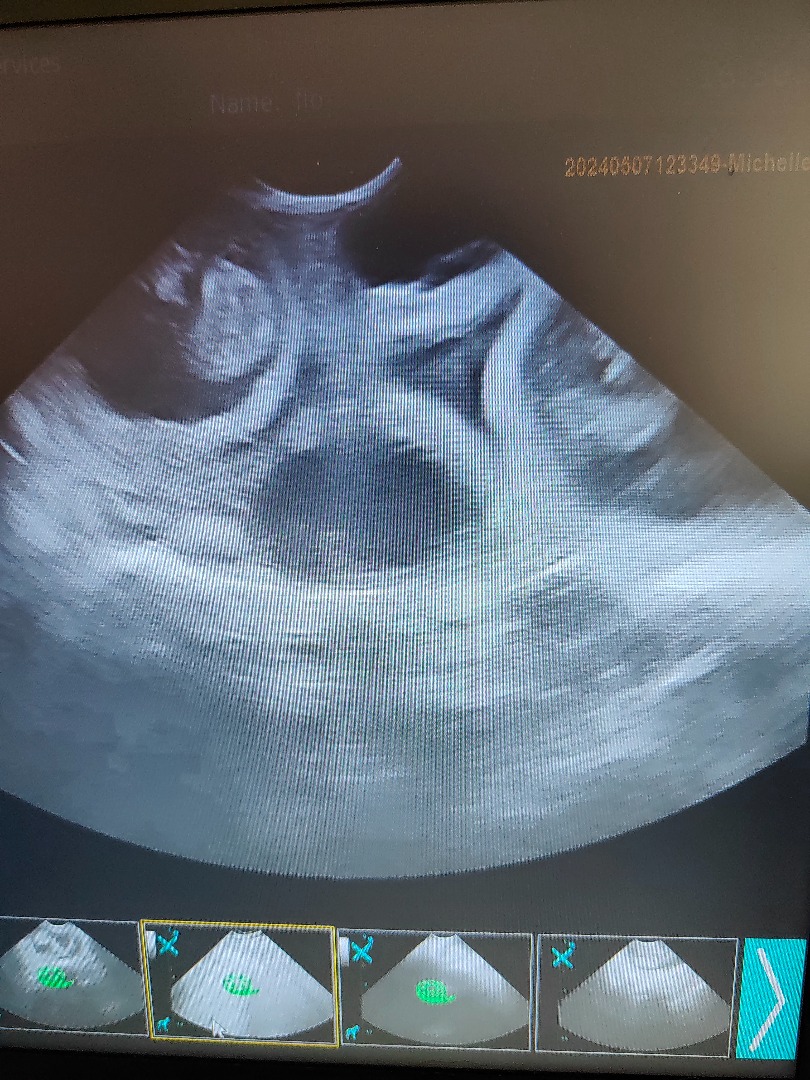

Urgent vet referral scan, no pups, lots of fluid, dog ended up have emergency operation